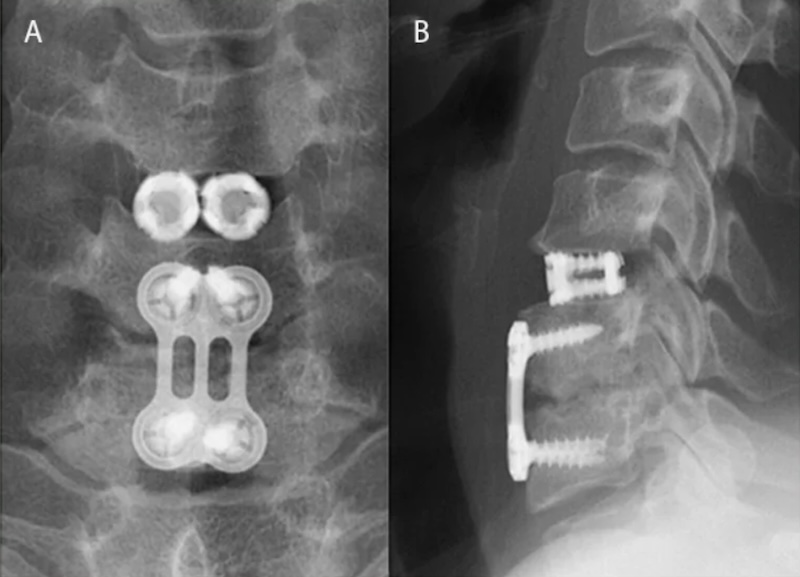

The VariLift-C is a Cervical Expandable Titanium spacer for use in the ACDF procedure and approved for use in the single level either with or without supplemental fixation and used singly or bilaterally. The cage has an external threads with large fenestrations for graft. The expansion plate expands the central core.

Configuration: Cage Alone , 0-Profile (Integrated screws)

Expansion: Expandable , Bi-Directional Expansion